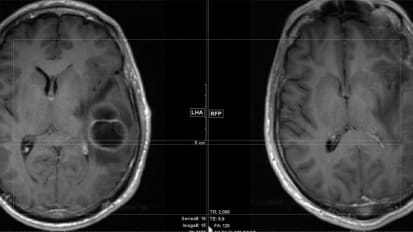

Awake Craniotomy with Fluorescent Guidance: A Case Study

Glioblastoma is the most common and lethal type of malignant brain tumor due to its aggressive nature and ability to rapidly invade surrounding functional brain tissue. One of the most important prognostic factors for patient survival ...